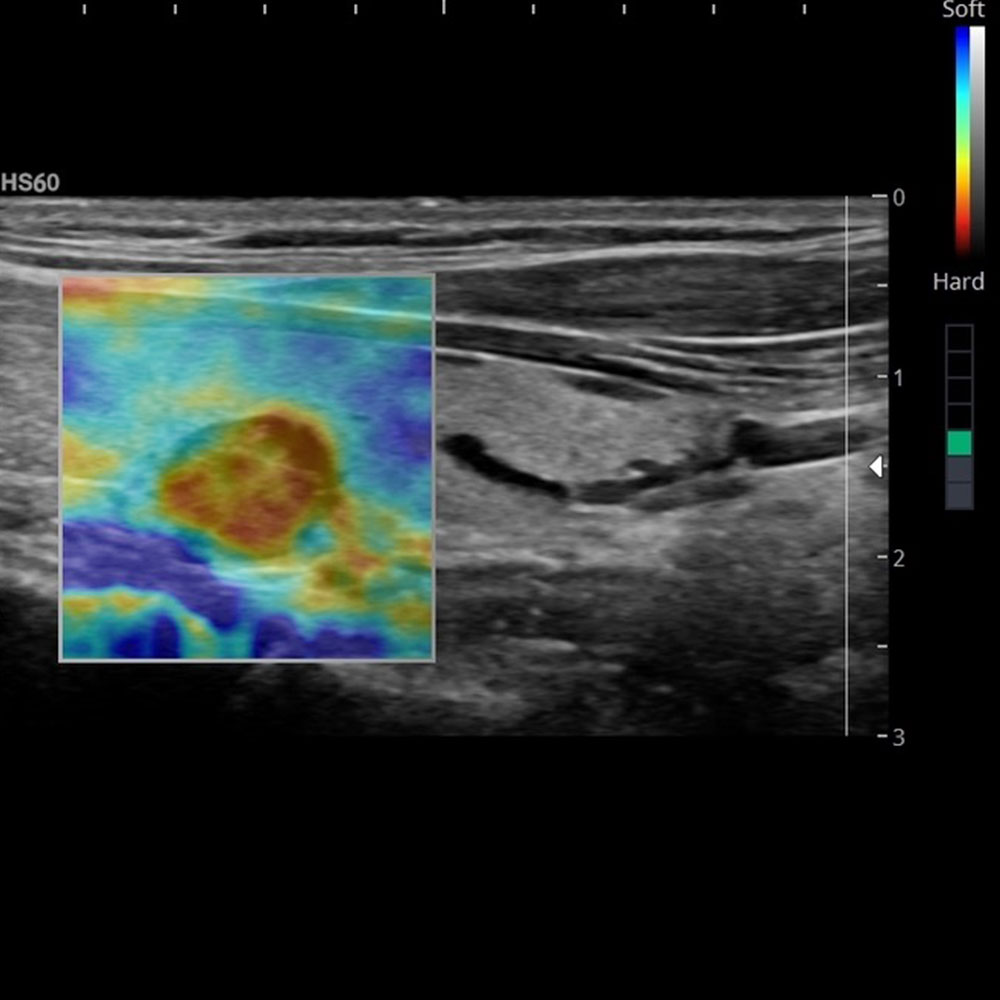

Elastographie der Leber (ARFI)

Chronische Lebererkrankungen können mit zunehmender Vernarbung des Lebergewebes bis hin zur Leberzirrhose führen. Durch die Vernarbungen wird die Leber härter. Mit der Elastographie kann der Härtegrad des Lebergewebes gemessen werden und somit das Ausmaß der Vernarbung der Leber bestimmt werden. Die gesetzlichen Krankenkassen bezahlen diese Untersuchung nicht.